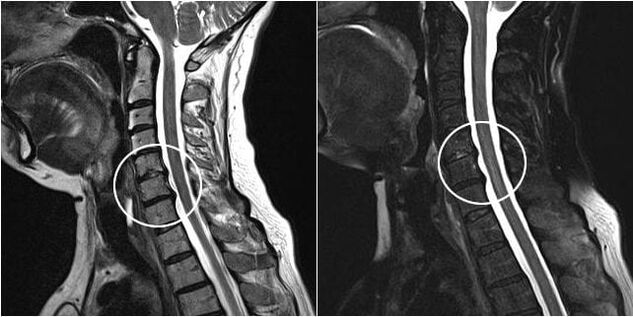

If a herniated disc is found, the question of an operation arises. This technique involves removing a hernia that compresses the root and creating conditions for its recovery.